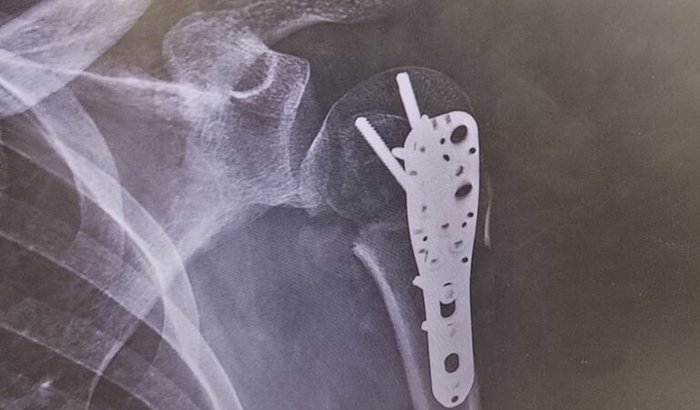

Olá, me chamo Jeremias e me acidentei dia 31/12/25. Estou sem trabalhar desde então e meu dinheiro acabou. Preciso de uma quantia ainda pra consertar minha motocicleta pra retornar as atividades. Embora ainda precise de algumas semanas, pro movimento do braço retornar a capacidade laboral. Fiz cirurgia no úmero e estou realizando fisioterapia. Tive gastos demais e quase nenhuma receita, tendo acabado minhas poucas reservas financeiras.